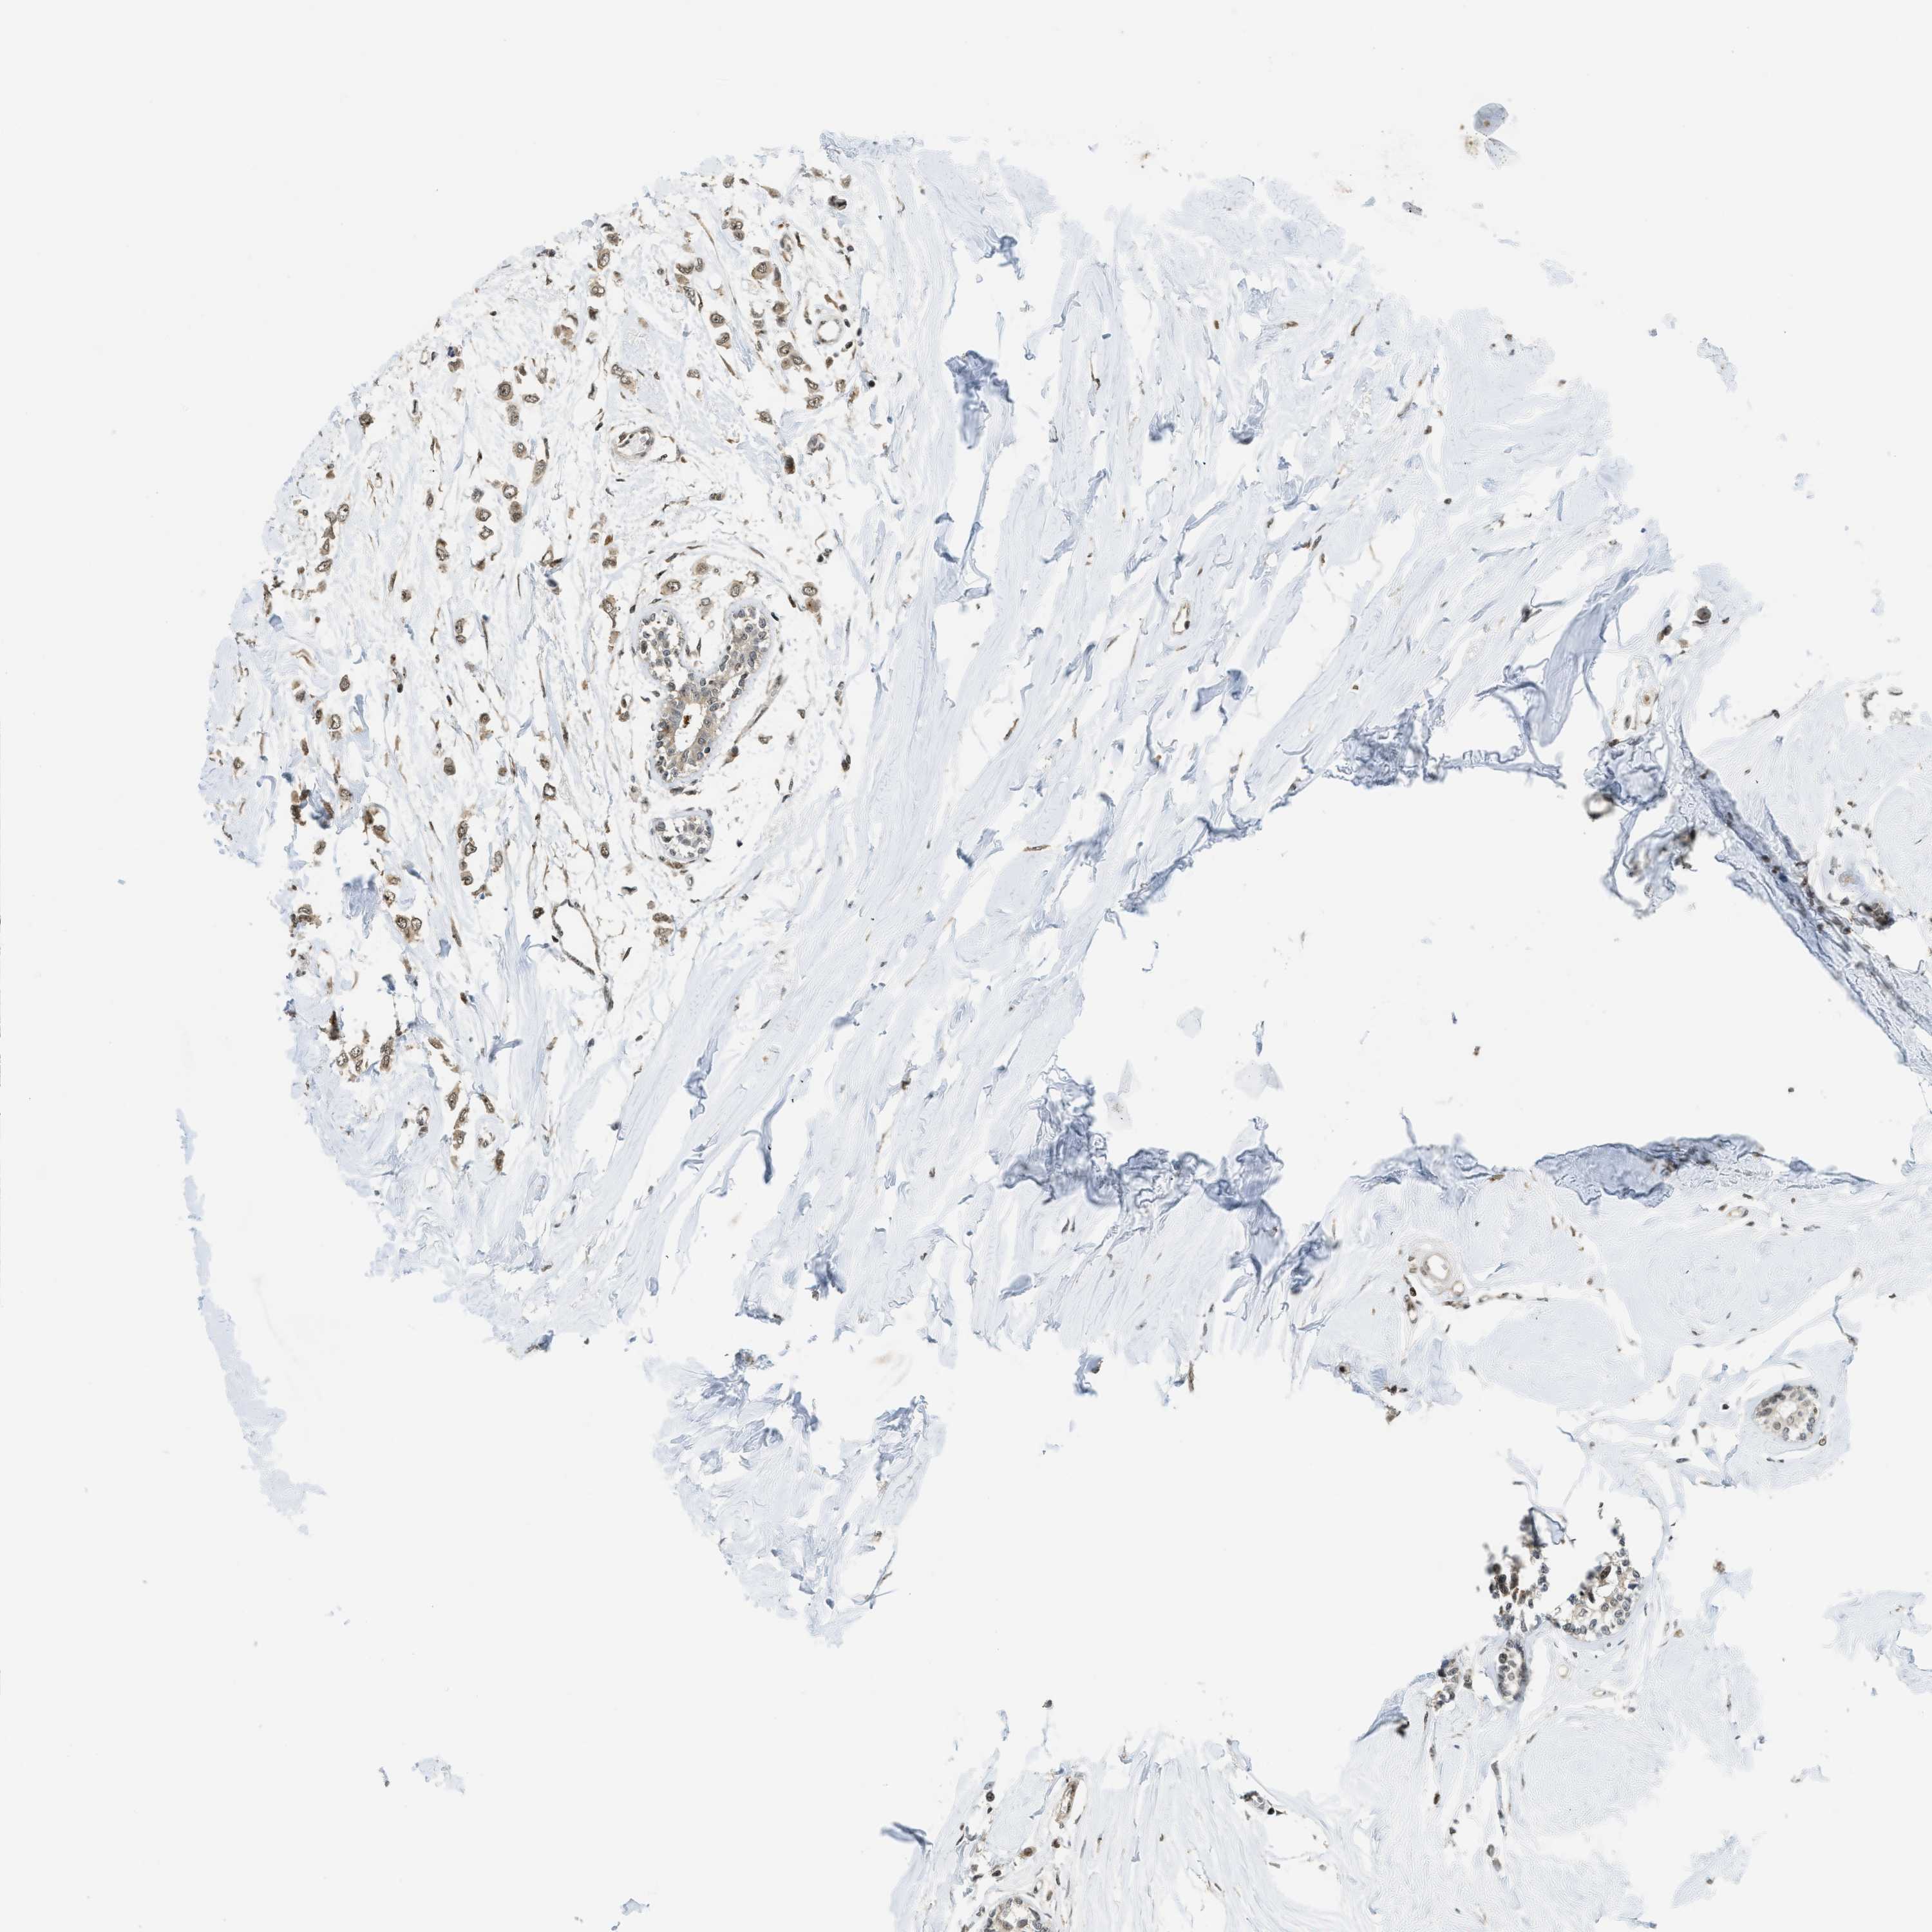

BRCA TCGA BRCA VALIDATION PROTEIN EXPRESSION

ANTIBODIES

AND

VALIDATION